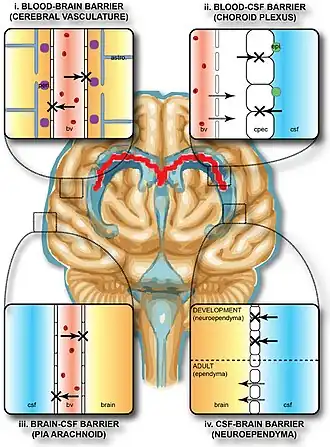

Blood brain barrier

The blood-brain barrier (BBB) is a semipermeable membrane that separates the blood from the brain’s interstitial fluid. It is formed by tight junctions between endothelial cells, astrocytes, and pericytes in the brain’s capillaries, and has high electrical resistance. The BBB is crucial for protecting the brain from pathogens and toxic substances, maintaining homeostasis, and preventing alterations to neuronal functions. However, some diseases can damage the BBB, causing leakage. Research suggests that increasing intake of vitamins and antioxidants, as well as reducing stress, can help restore the BBB. Due to its selective nature, the BBB restricts the passive diffusion of solutes, large and hydrophilic molecules, and immune factors, making it challenging to deliver pharmaceuticals directly to the brain.[6]